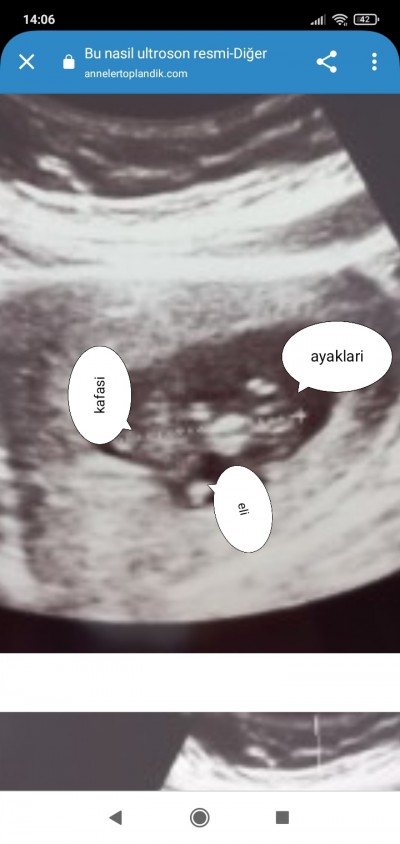

Ortada kalan govdesi. Bacaklarini karnına ,elinin birini de ağzının o tarafa çekmiş

image

Ya çok tes3kkur ederim burda arkası dönük sanırım hareket ediyordu baya çok sagolun :))

(1,145 puan) tarafından

Çok hareketli oluyorlar uygun pozisyonu yakalayıp durdurup foto anca alıyorlar . Ben de ultrasonda çalıştığım için biliyorum. Çok heyecanlı zamanlar oluyor doktorun odasına girince bebeği görmek .siyah beyazların içinde neresi ne diye düşünmek .. siz yargilayanlari bosverin. Sağ salim zamaninda gelir kucağınıza insaaallah